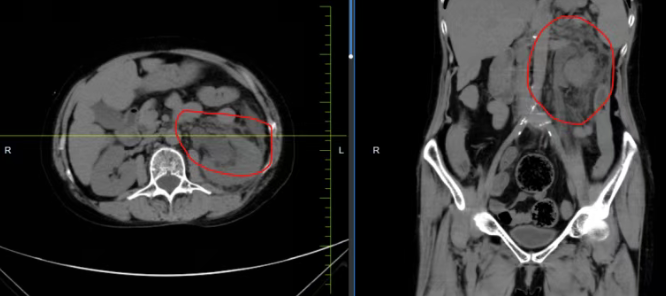

该患者因左侧重复肾畸形合并输尿管上段结石,造成尿路梗阻、肾盂积水,细菌逆行感染引发急性肾盂肾炎、肾周围炎,最终诱发脓毒血症。同时患者合并高血压病3级、低蛋白血症等多种基础疾病,治疗难度显著增加。